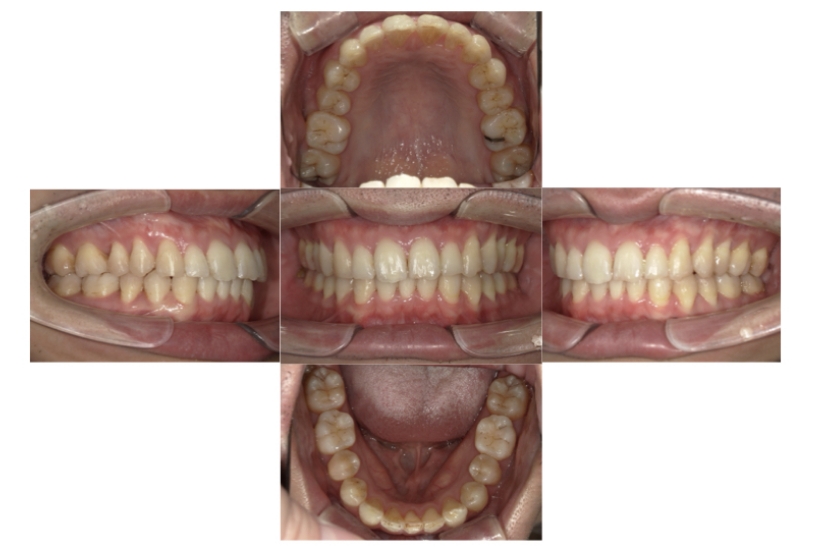

症例2

上下顎前突、叢生

抜歯

ブラケット矯正

上下顎前突、叢生(上下出っ歯、上下の前歯のガタガタ)のケースです。

装置はラビアル(上下表側)で、上下顎の小臼歯を4本抜歯を行っています。抜歯したスペースを使って、上下の前歯の後方移動と叢生(ガタガタ)の改善を行っています。

主訴 前歯のガタガタと口元がでているのが気になる。

年齢・性別 30歳 女性

お住まいの地域 東京都大田区

治療方針 抜歯スペースを利用して上前歯の叢生(ガタガタ)と口元突出の改善

抜歯部位 上下顎左右第一小臼歯

使用装置 ラビアル(上下表側)、顎間ゴム

治療期間 1年11か月

治療回数 13回

リテーナー クリアリテーナー

BEFORE

AFTER